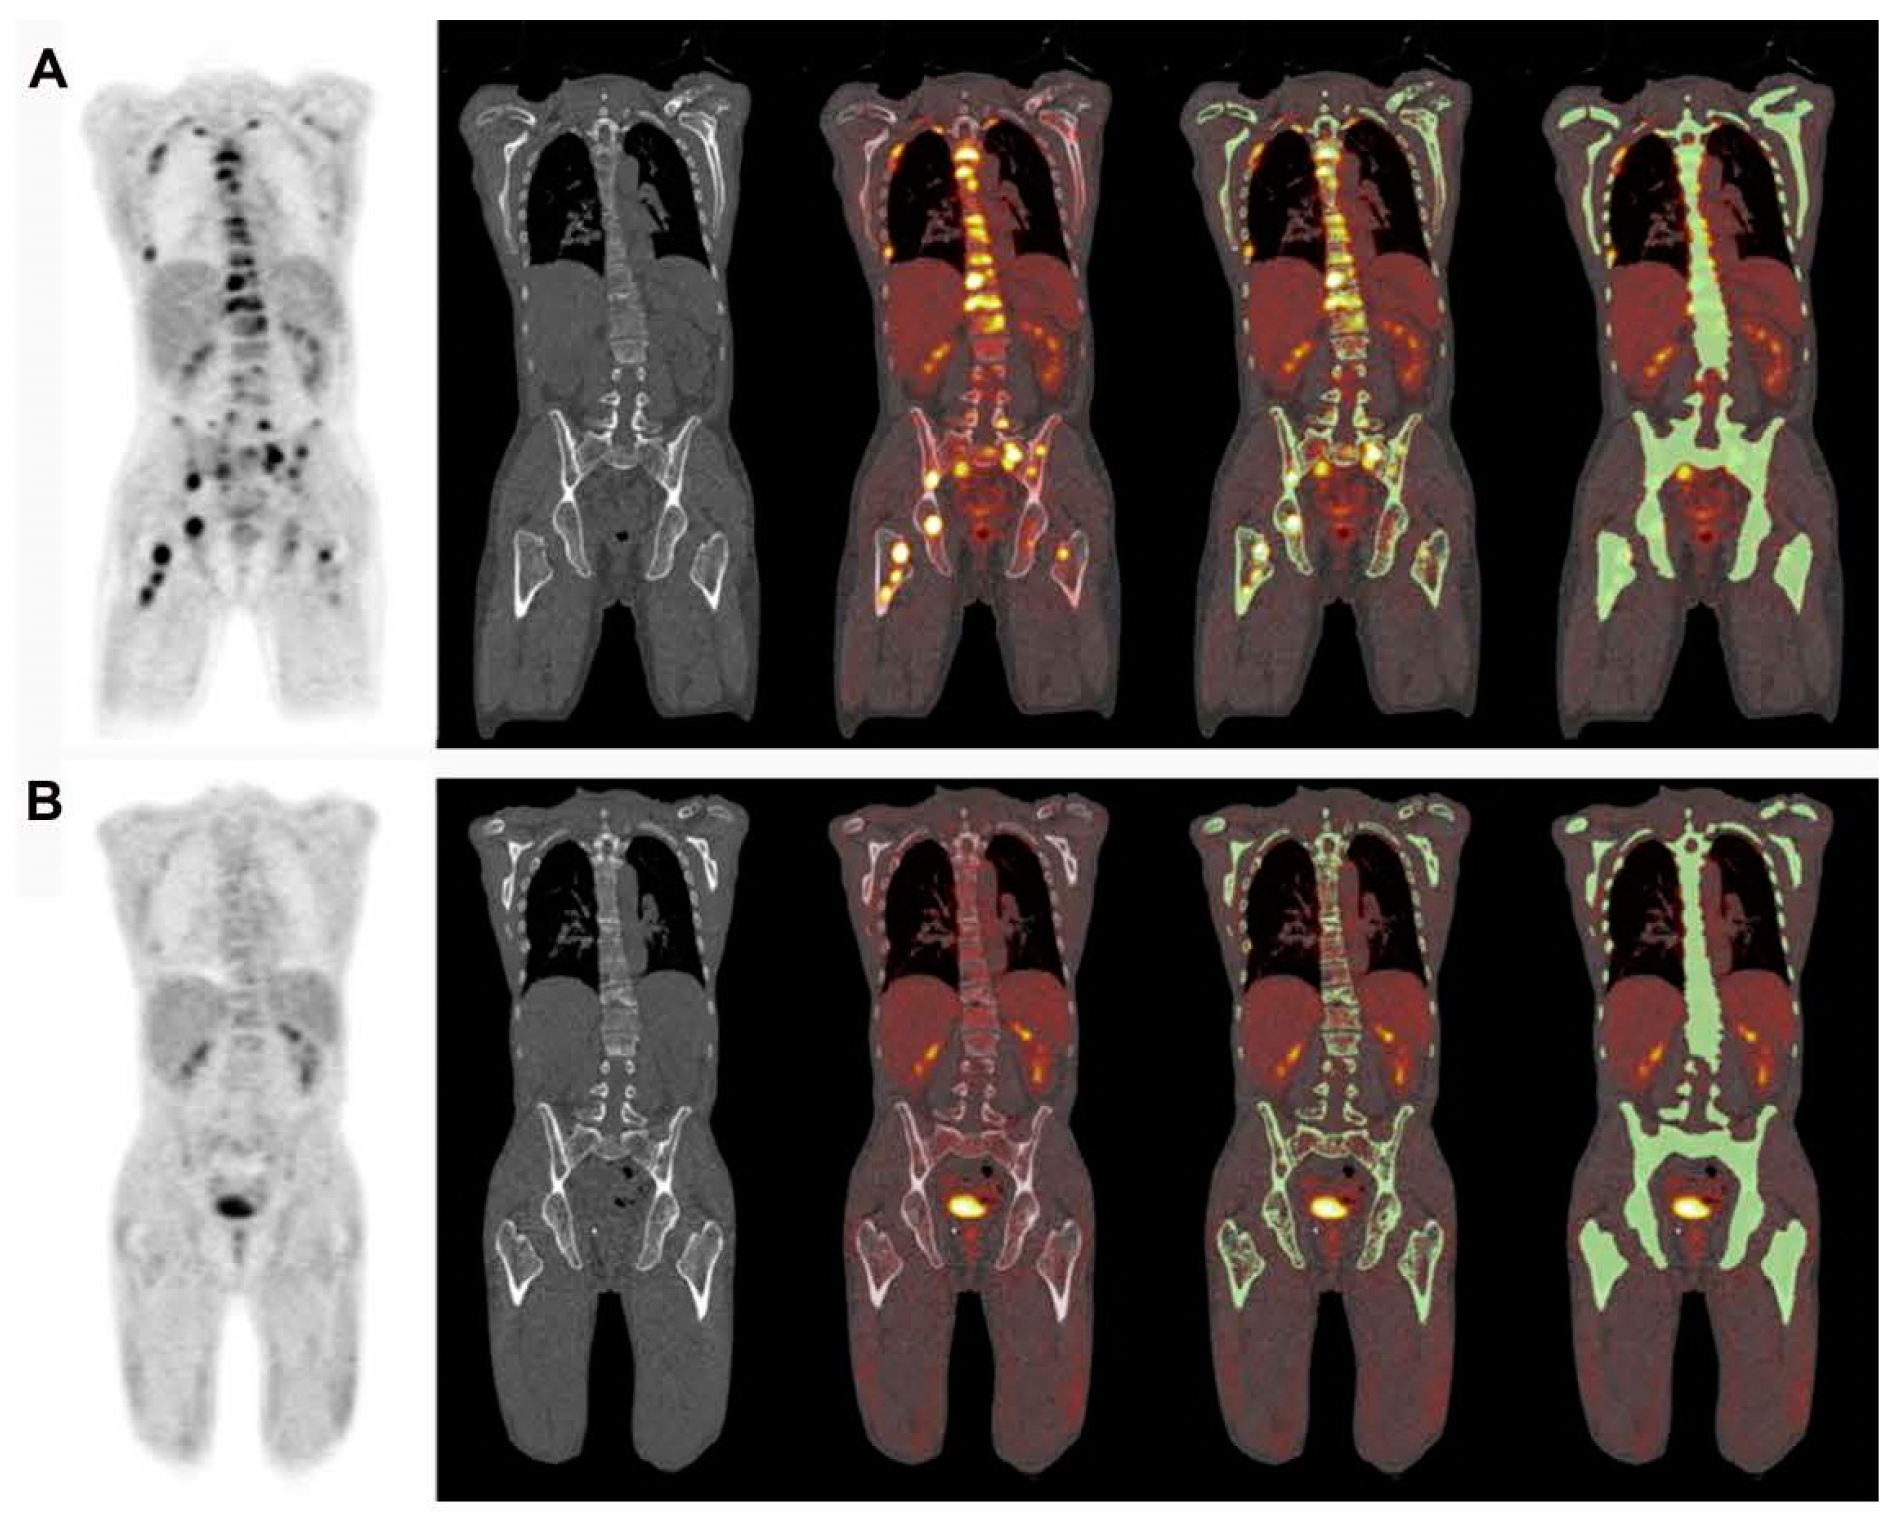

4. Importance of [18F]FDG PET/CT in Assessing Treatment Efficacy

4.2. Assessment of Myeloma Patients after Treatment

5. Identification of Minimal Residual Disease (MRD) in Myeloma